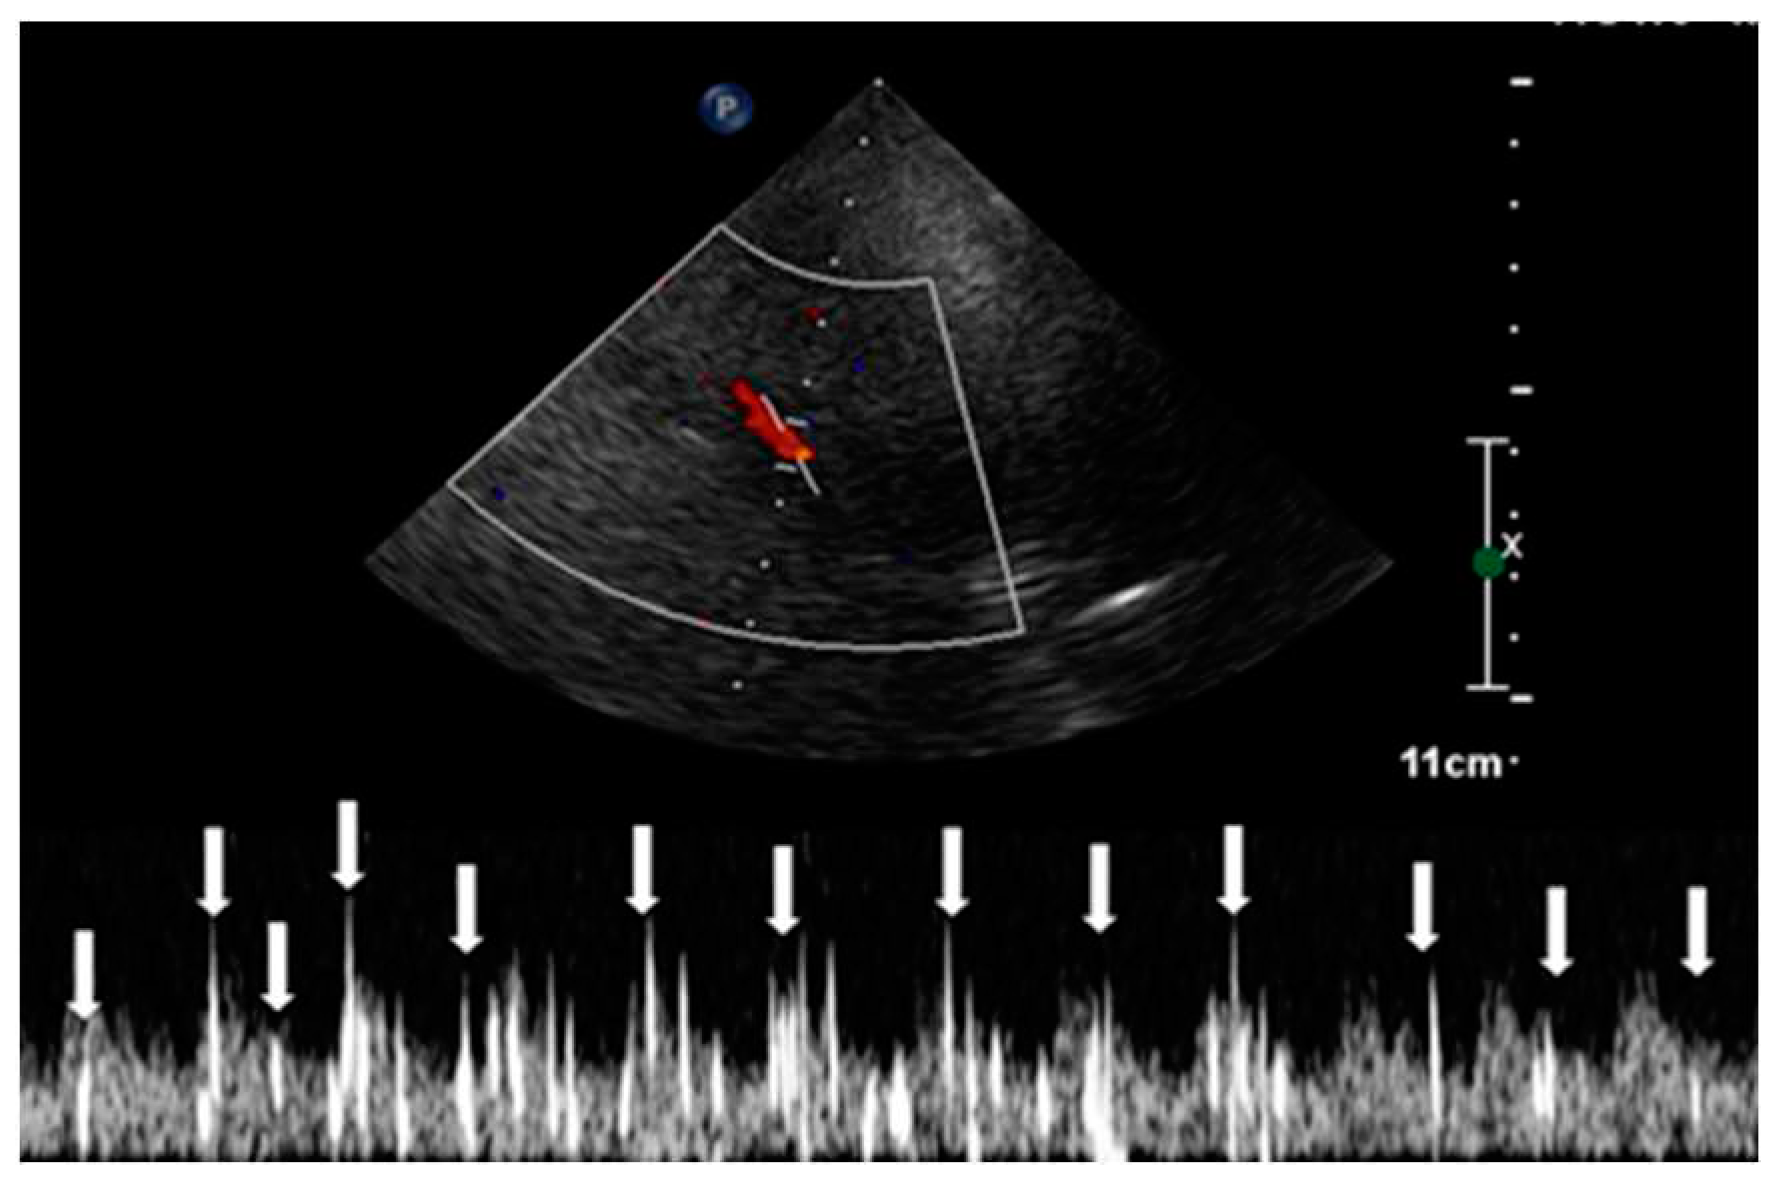

This procedure was facilitated by imaging through the squamous section of the temporal bone. The detection of high-intensity transient signals (HITS), which indicate the presence of microbubbles, was conducted by assessing the middle segment of the right middle cerebral artery using TCCD (Figure 4).

The observation window for each scan was set to a duration exceeding 30 seconds, monitoring the occurrence of HITS within the vessel [24]. The assessment of RLS through the identification of HITS was quantified using the Spencer Grading Scale, a system that includes different grades. Each grade corresponds to a different degree of microbubble identification [25]. In this specific case, HITS were not detectable under resting conditions. However, during the Valsalva stimulation test, the presence of HITS was visually confirmed. A total of 37 instances of HITS were recorded, resulting in a grade 3 classification for the PFO-induced RLS. Consequently, the diagnosis of C-TCCD indicated the presence of an intracardiac short circuit caused by the PFO condition (Figure 5.).

Figure 4. Transcranial color-coded doppler with pulsedwave spectral doppler of the middle cerebral artery.

Figure 5. High-intensity transient signals (HITS) caused by microbubbles in the TCCD contrast and right-to-left shunt positivity.